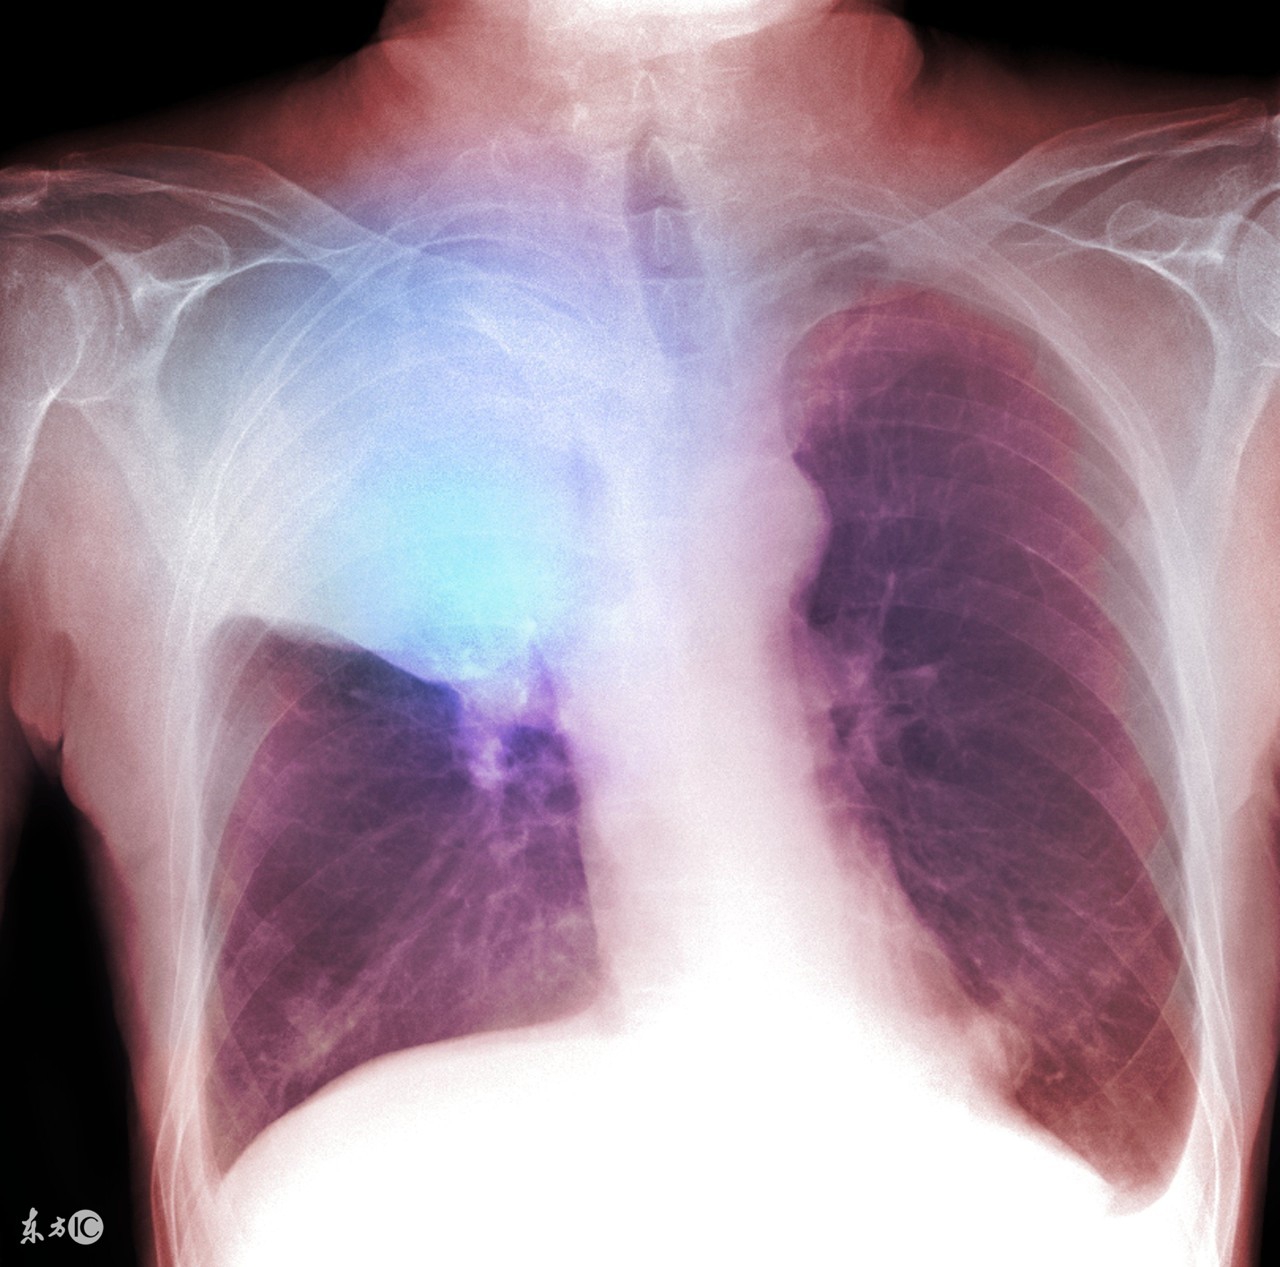

肺癌发热不能小看

相对于其他癌症而且,肺癌的发热原因可以明确到以下两点:

肿瘤逐渐增大阻塞支气管就会出现阻塞性肺炎,这就是炎症引起的发热,如果通过抗生素治疗是可以控制体温的,但如果不彻底解决阻塞支气管的肿瘤,就会复发;

2.再有就是所谓的癌性热,癌性热一般是以低烧的形式出现的,也就是温度低于38.5℃。虽然能通过物理降温的方式控制低烧,但这类的发热一定要通过对癌症根本性的治疗才能得到有效控制。